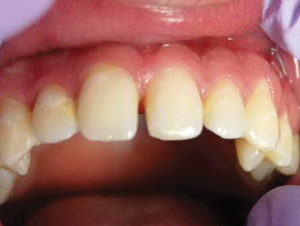

Un nuevo paciente de 7 años presentó una importante descomposición e hipocalcificación en el primer molar permanente superior derecho. Durante mucho tiempo se ha demostrado que los primeros molares permanentes cariados e hipocalcificados en pacientes pediátricos le dan al profesional un dilema restaurador difícil. ¿Deberíamos intentar prepararnos y restaurarlos conservadoramente? ¿Deberíamos ser más agresivos y restaurar con una cobertura completa como una corona de acero inoxidable bien adaptada? Activa proporciona una gran alternativa en estos casos, con liberación de calcio, fosfato y fluoruro junto con alta resistencia y resistencia a la fractura.

Figura 1. Después del ataque ácido y el uso del agente de unión Scotchbond Universal (3M), los dos molares primarios superiores se restauraron con Activa Bioactive Restorative A2. |

Figura 2. Una vez que se excavó la descomposición y se colocaron los márgenes en superficies sólidas, se colocó un bisel pesado en el esmalte para aumentar la resistencia de la unión y la integridad marginal. El área oscura central era sólida. El diente estaba revestido con una base / revestimiento Activa. |